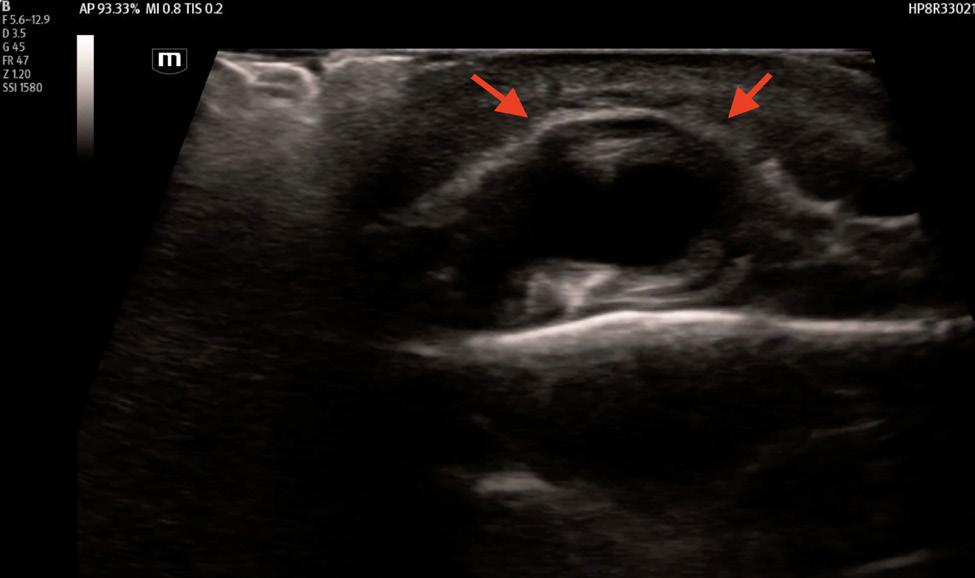

352 Point-of-care Ultrasound Clarified the Diagnosis of an Occipital Artery Pseudoaneurysm After Blunt Trauma

K Nix, S Johnson, D Perling, B Parkinson, H Studebaker, B Foster

355 Point-of-care Ultrasound Diagnosis of Cardiac Myxoma

J Brutico, D Kreider